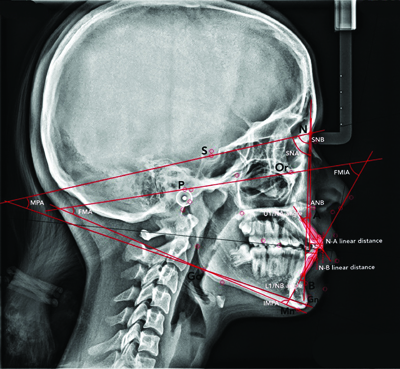

Parameters measured on lateral cephalograms: Sella, Nasion, A point (SNA), Sella Nasion B Point (SNB), A Point, Nasion, B Point (ANB), Mandibular Plane Angle (MPA), the upper incisor to NA (U1/NA) angle and linear distance, the lower incisor to NB (L1/NB) angle and linear distance, the Frankfort-mandibular Plane Angle (FMA), the Incisor-Mandibular Plane Angle (IMPA), and the Frankfort-mandibular Incisor Angle (FMIA). These measurements were taken at T1 and T2 [Table/Fig-2,3].

Lateral cephalogram showing SNA, SNB, ANB, Mandibular Plane Angle (MPA), upper incisor to NA (U1/NA) angle and linear distance, lower incisor to NB (L1/NB) angle and linear distance, Frankfort-mandibular Plane Angle (FMA), Incisor-mandibular Plane Angle (IMPA), and Frankfort-mandibular Incisor Angle (FMIA).